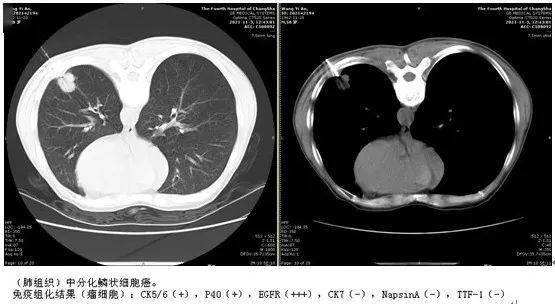

肺结节检查报告图片